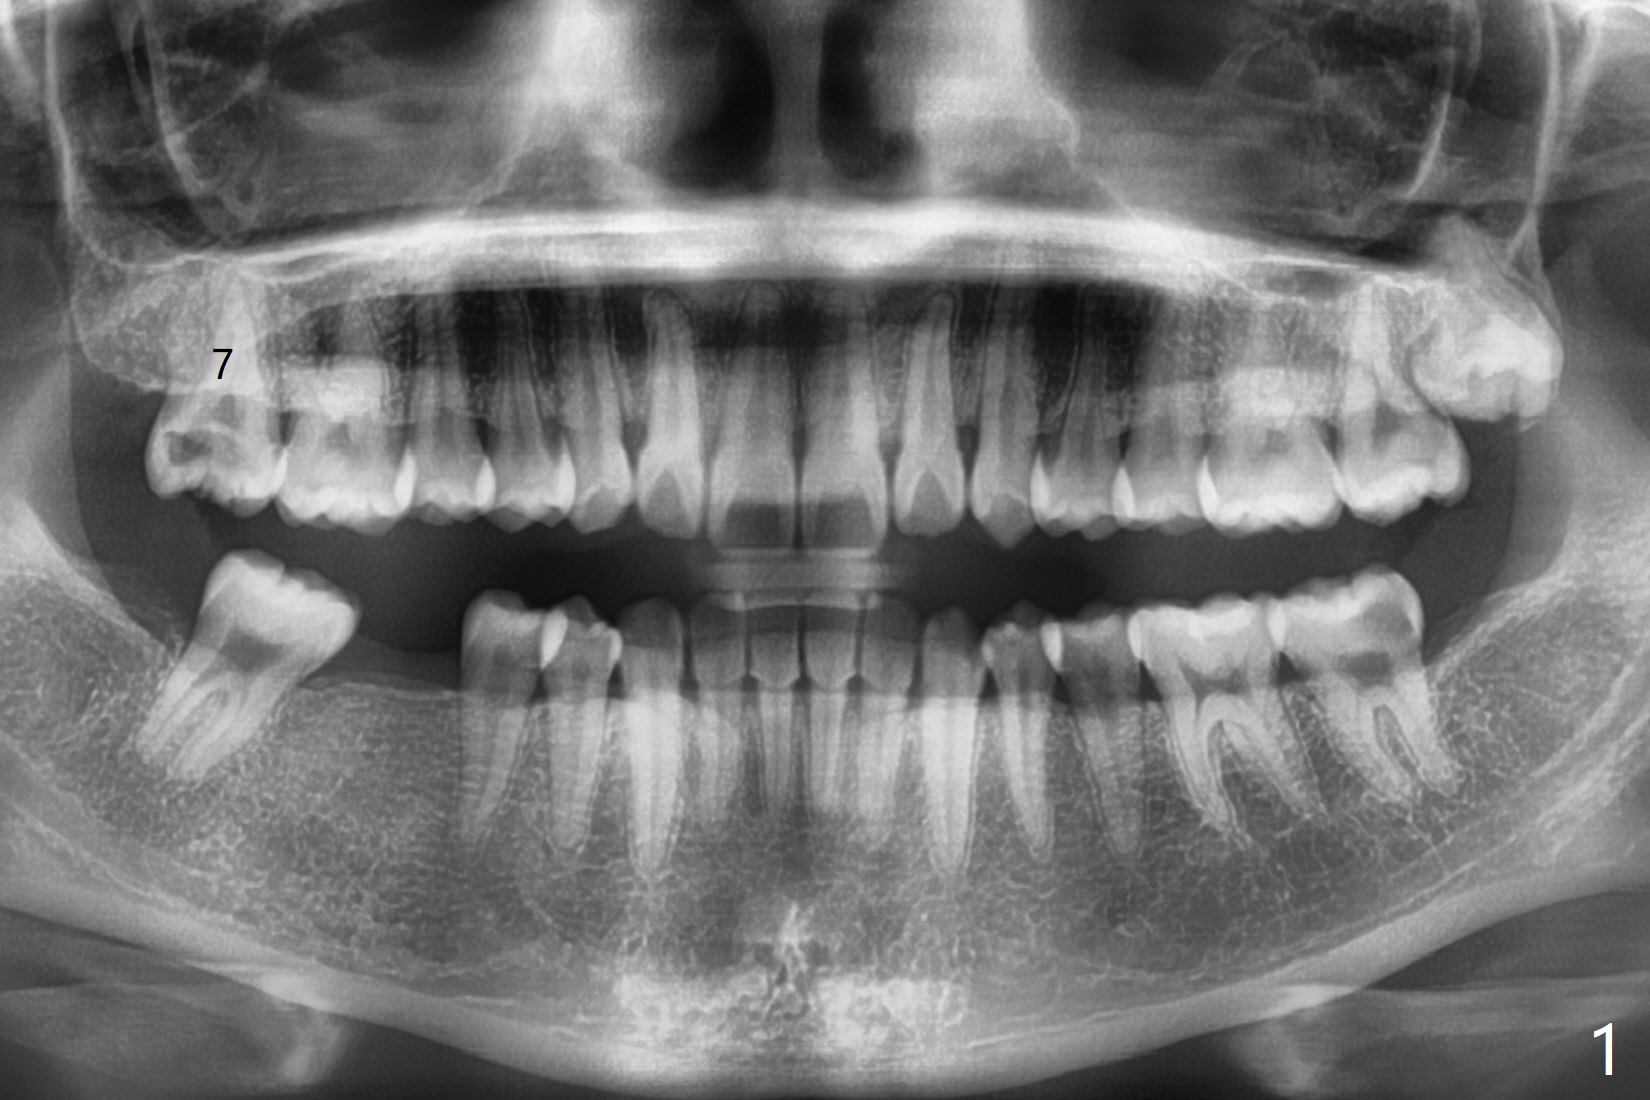

23岁女留学生,即将毕业回国,右上7夜间痛(图一),远中龈下龋,牙龈增生,局部垂直距离小。两三天考虑后,她回来深洗(图二),同意拔除,植骨(皮质,图三),放置GEM Cap,牙周胶水固定,有限垂直距离,肥大颊粘膜,觉得缝合困难。放置间隙保持器必须压到胶原膜,牙周敷料必须放置,防止保持器颊侧臂刺激粘膜。上颌第二磨牙植骨很麻烦,如果使用粘性骨粉,就方便多了。在做深洗时,可以抽血制备PRF,不浪费时间,但愿效果好(信则灵)。